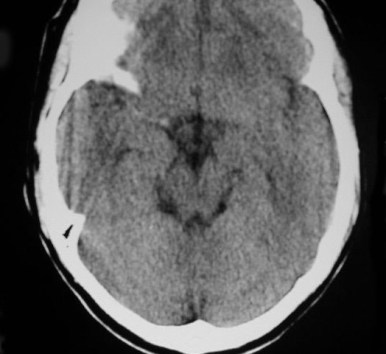

Signo visible en la TC craneal sin contraste. Fue inicialmente descrito por D.H. Yock en 1981 y corresponde a la alta densidad de la primera porción de la arteria cerebral media (ACM) comparada con la arteria contralateral, y es un signo de isquemia cerebral por oclusión arterial por trombo o émbolo, cuya densidad (80 UH=unidades Hounsfield) es más alta que la de la sangre circulante(40 UH) por la mayor cantidad de fibrina y proteínas y la menor proporción de suero.

Es un signo precoz de accidente cerebro-vascular (ACV), aparece en las primeras 6 horas y deja de verse en el ACV evolucionado, por la resolución del trombo.

Este signo tiene casi un 100 % de sensibilidad pero solo un 30 % de especificidad.

Se ha visto, como falso positivo, en pacientes asintomáticos con poliglobulia o deshidratación, por el aumento del hematocrito, aunque en este caso es bilateral. En pacientes con arteriosclerosis y calcificaciones vasculares, la apariencia de la ACM puede parecer hiperdensa. También se ha descrito en algún paciente con encefalitis por herpes simplex, que característicamente afecta al lóbulo temporal.

Imagen del mismo paciente 2 días después del primer estudio. Se observan un área hipodensa por infarto en el territorio de la ACM derecha.